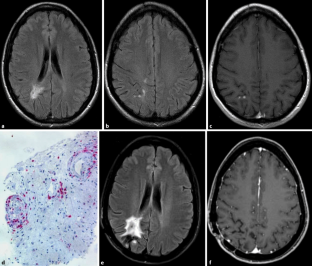

Abb. 2